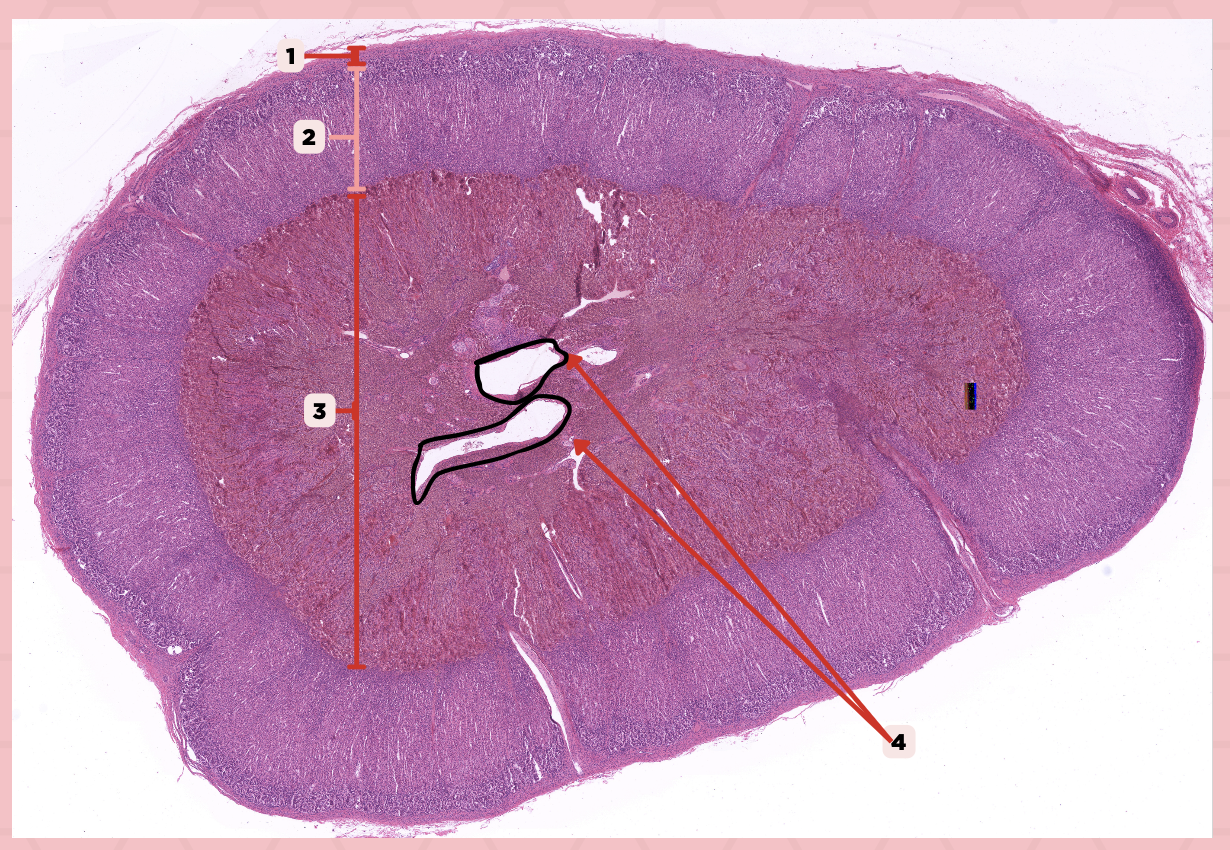

Adrenal

Identify the specimen.

Connective Tissue Capsule

Identify the structure labeled as 1.

Cortex

Identify the structure labeled as 2.

Medulla

Identify the structure labeled as 3.

Medullary Veins

Identify the structure labeled as 4.

Zone glomerulosa, Zone fasciculata, Zona reticularis

What are the zones present in pointer #2?

Catecholamines

What hormones are produced by pointer #3?